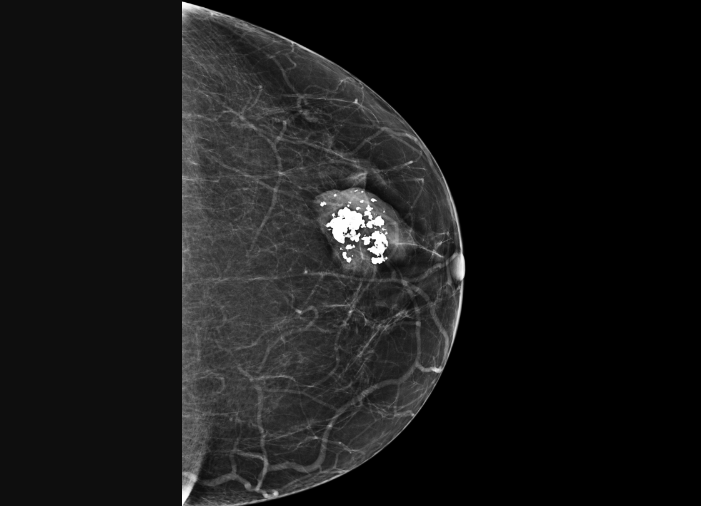

Для злокачественных микрокальцинатов характерна: неоднородная структура, нечеткость и неровность (оскольчатость) контуров, непохожесть друг на друга (полиморфность), сгруппированность, т.е. локальная высокая их плотность.

Рак молочной железы.

Крупные неоднородные кальцинаты или мелкие линейные, удлиненные игольчатые, или ветвящиеся имеют повышенный риск злокачественности. При раке молочной железы кальцинаты также часто имеют мелкоточечный вид, напоминая песчинки неправильной формы. С увеличением числа микрокальцинатов на единицу площади вероятность рака возрастает: при количестве 15 микрокальцинатов на 1 см2 и более вероятность рака достигает 80 %. Скопление тонких линейных кальцинатов также сопровождается высоким риском рака молочной железы.

Подозрение на рак молочной железы усугубляется при сочетании микрокальцинатов с нарушением структуры ткани молочной железы или ее уплотнением.